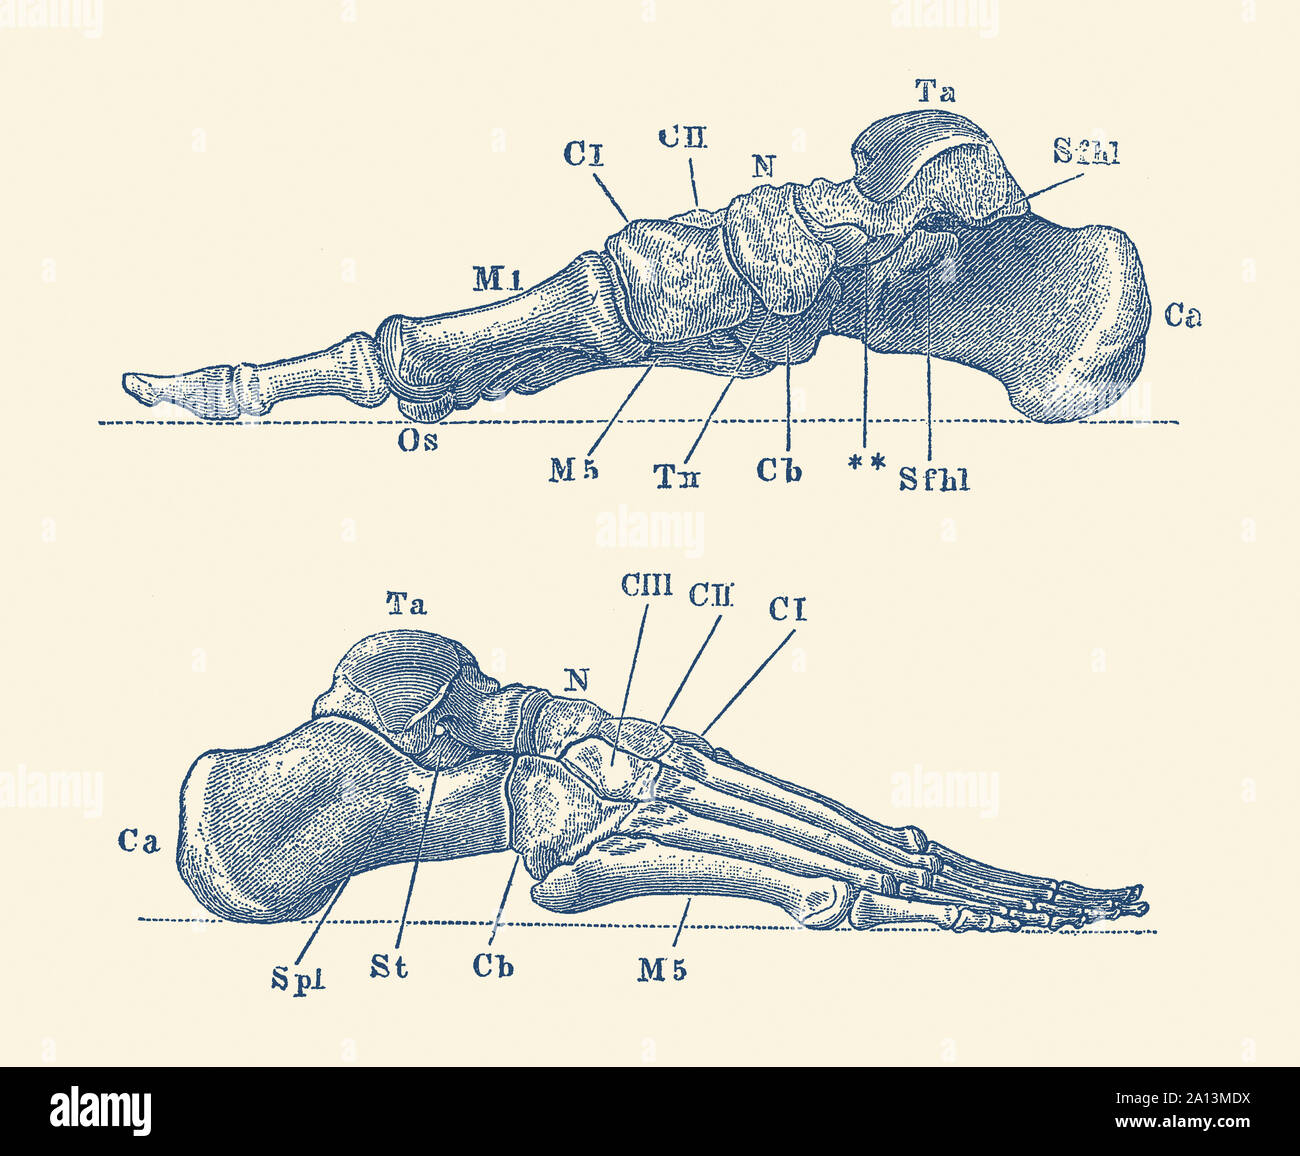

RF2BTGWJJ–Schéma d'un pied humain, l'un est la vue de côté et l'autre a de la semelle, dessin de ligne vintage ou illustration de gravure.

RM2A83MWT–Opinions de l'os dans le pied humain, de la cheville aux pieds. La gravure sur cuivre par Edward Mitchell après une illustration anatomique par Jean-Joseph Sue de John Barclay's une série de gravures du squelette humain, MacLachlan et Stewart, Édimbourg, 1824.

RMK228DY–Partie terminale du membre inférieur, reposant sur le sol au cours de posture droite ; le squelette du pied a 26 os.

RFR362W5–Vintage illustration de l'anatomie, le pied droit de l'os, dorsalis et unique vue avec des descriptions anatomiques Italien